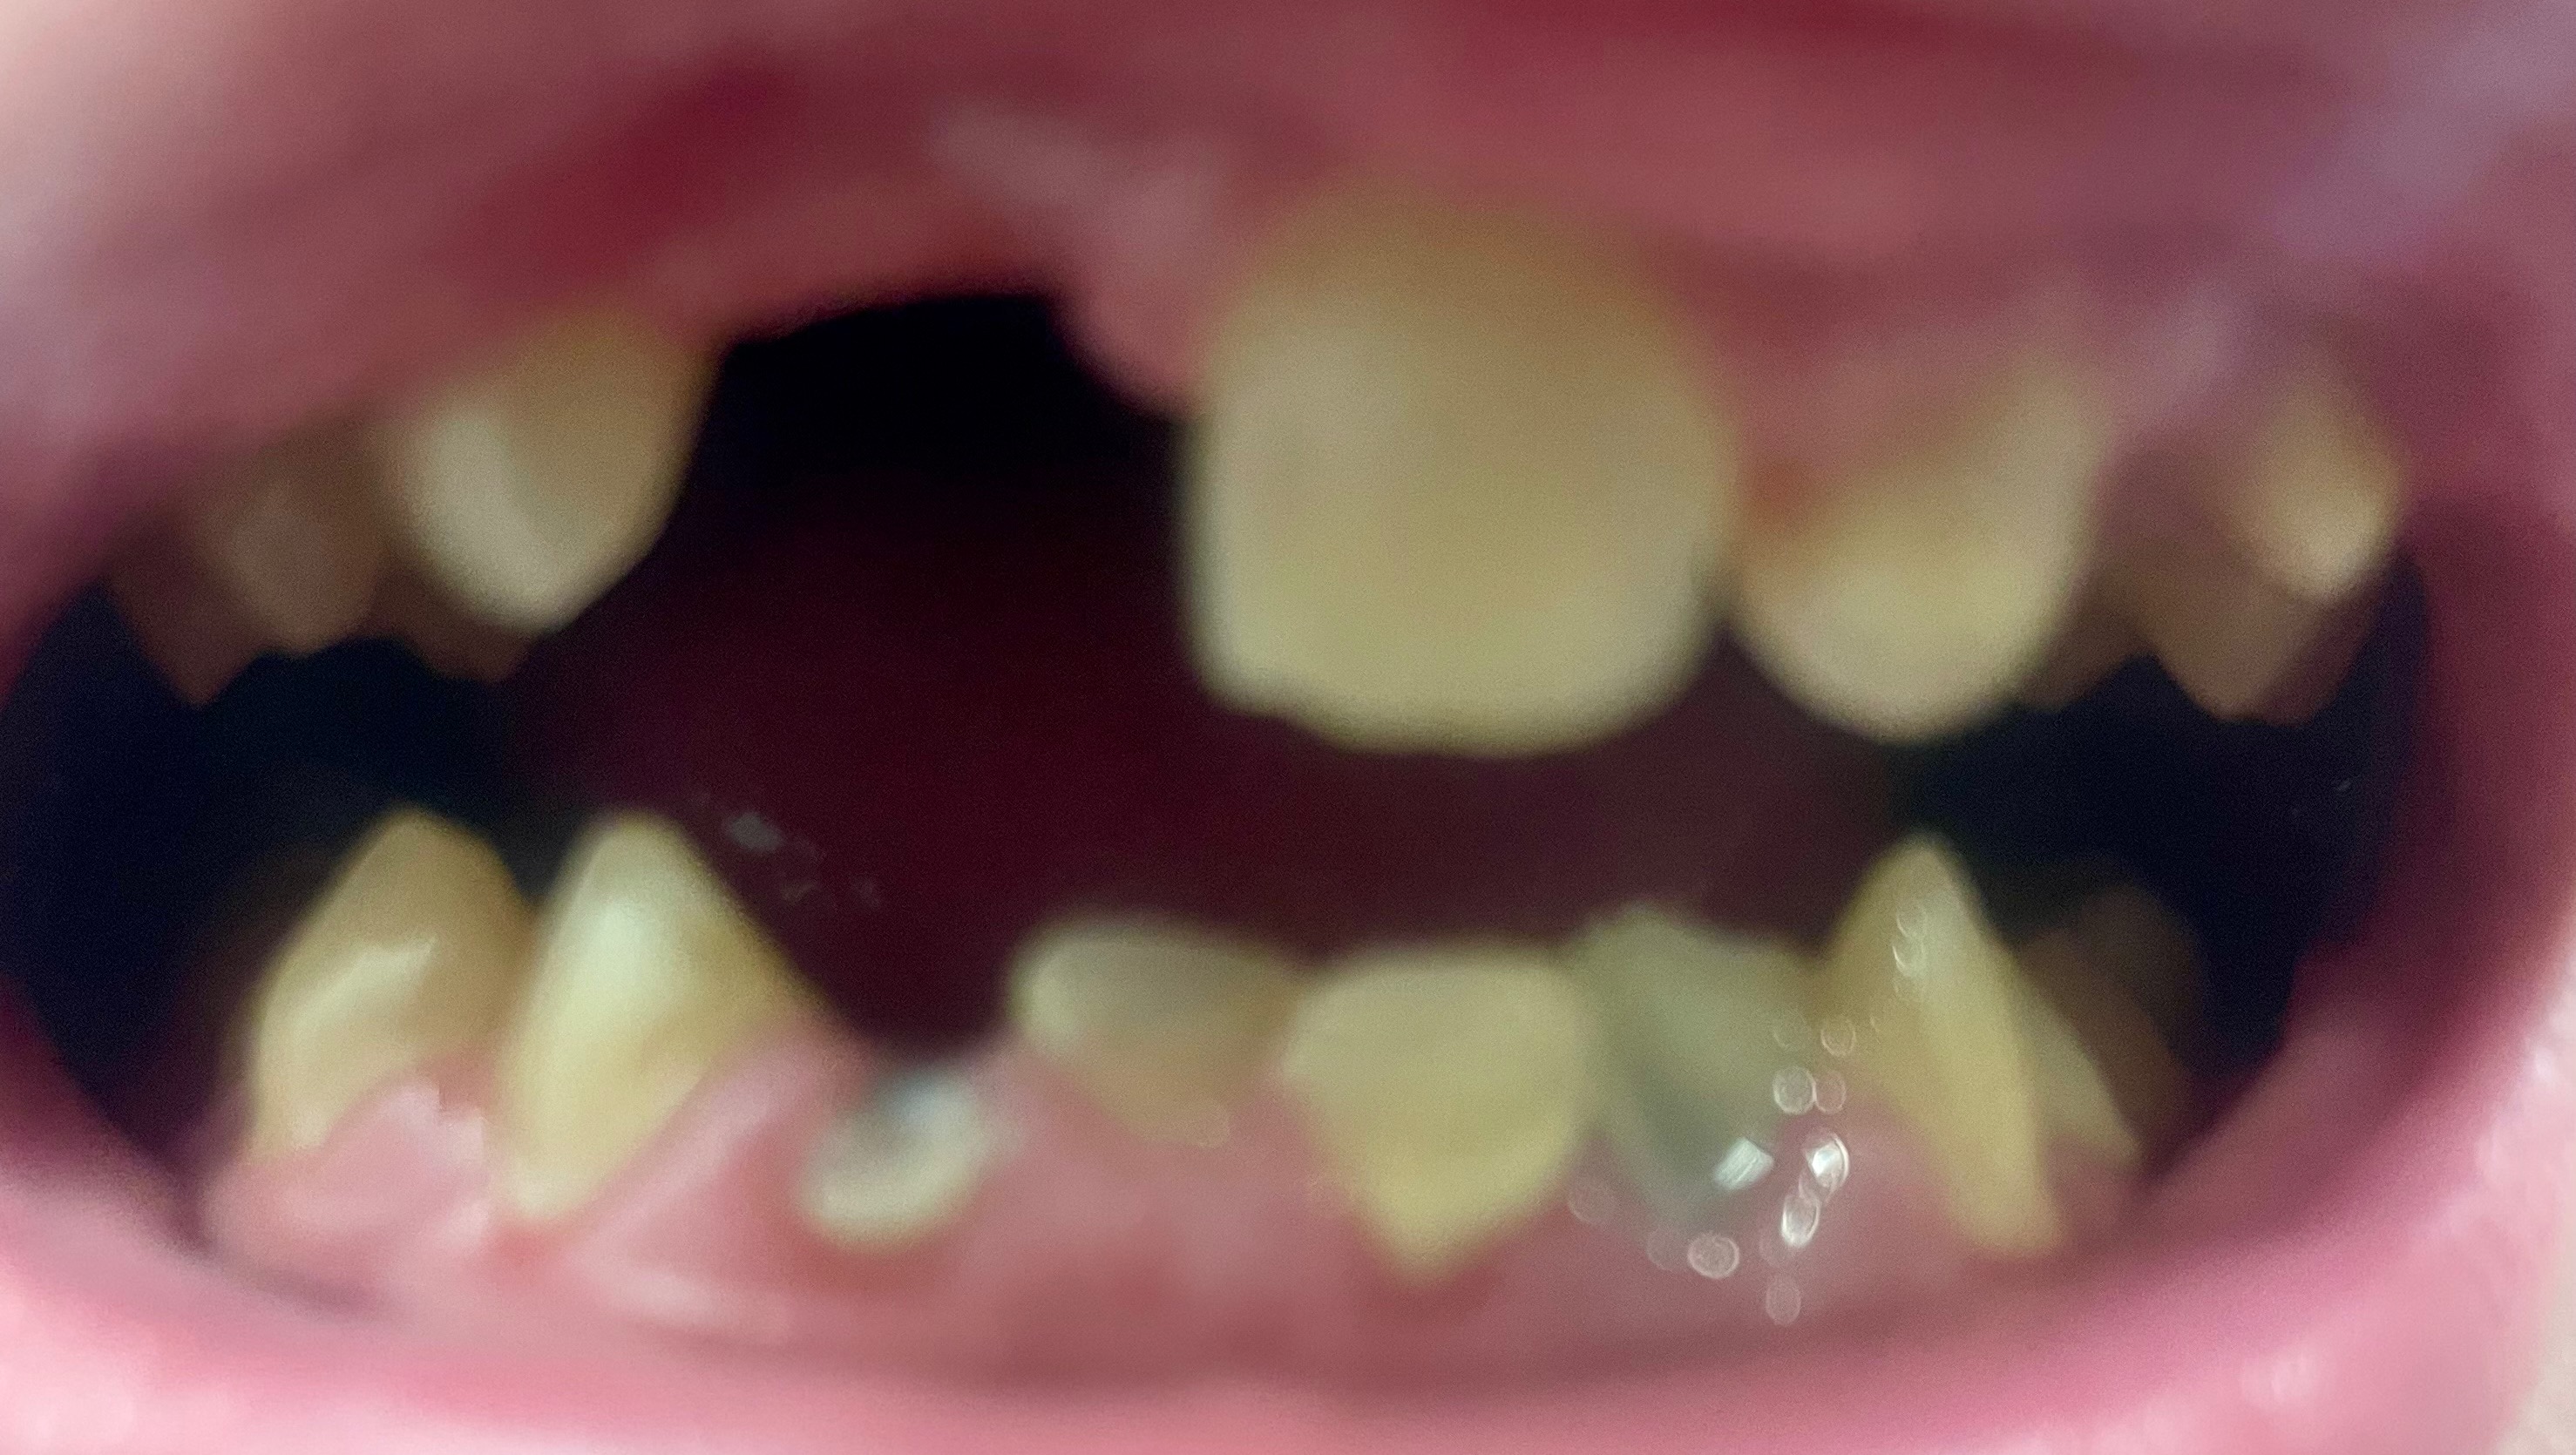

One thing has never been the same though. One thing that has not only never gotten better, but only worsened over time. The reason I can’t smile in front of others, sing in front of a crowd, or eat most foods like a normal person. I live in near constant pain and anxiety. I can’t even look at myself in the mirror most days, to be fully honest.

My teeth.

At the time, my family simply did not have the $25,000+ it would have cost to properly repair the damage. I had 11 teeth fractured, and one knocked completely out, along with severe facial trauma. So, we did a band-aid fix, filing my teeth down so they were no longer sharp, and performing root canals on all of them, with the hope that this would buy me 2-4 years of function.

As luck would have it, we managed almost 7, before the problems started catching up to me. A few months ago, I bit into a sandwich, and one of my front teeth fell out. A few months later, another started coming loose. The way it’s looking now, I will go from a jagged smile, to completely toothless by 2026.

There is no hope for the remaining incisors; they are too far gone and have to be removed. Even with insurance, working full-time, and going to a low-cost dental school, I am still looking at a $15,000+ out-of-pocket expense, over the course of two dozen surgeries, that will take approximately 3 years to complete.

(Attached are pictures of my injuries, X-rays, current state of my teeth, and a normal picture of me for reference. It’s gross, be warned lol. Thank you for looking)